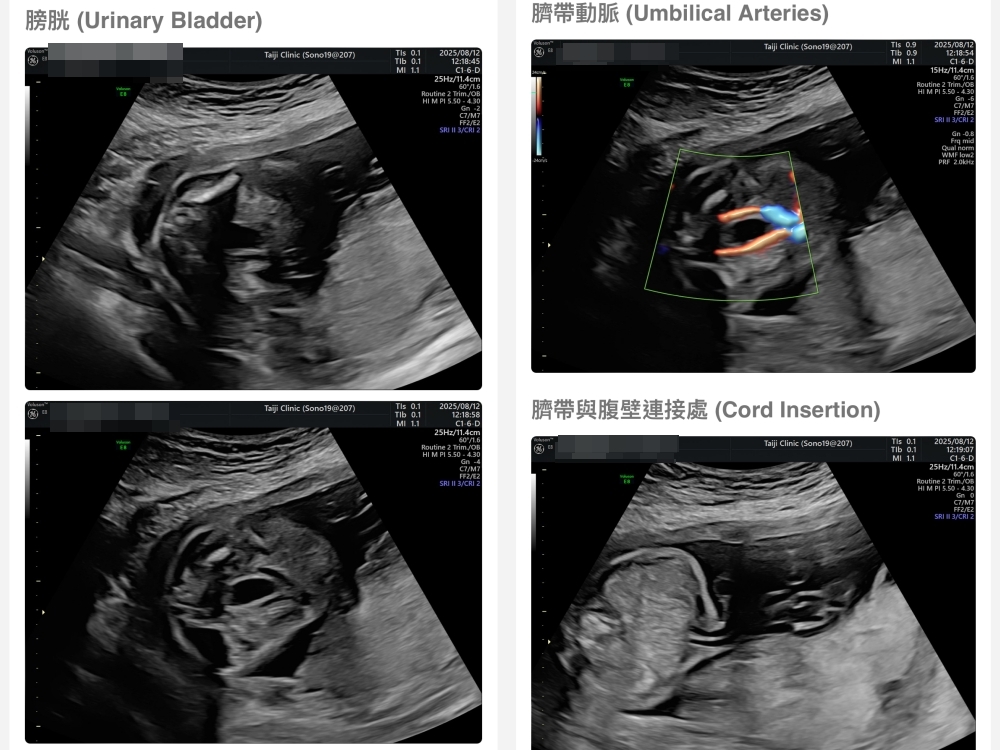

【台兒|高層次超音波|檢查結果】

▲離開診所後會收到MAIL,我們14:05離開,大約是16:45收到mail,裡面會有滿滿的超音波照片,紀錄的很詳細!也會提供紙本的報告,可以給日後產檢的醫師做參考👌